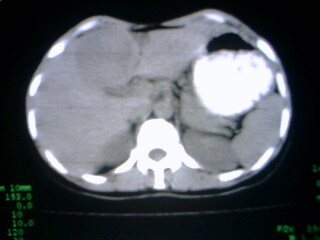

标题: CT9794:女 35Y 近两个月腹痛纳差明显消瘦 [打印本页]

标题: CT9794:女 35Y 近两个月腹痛纳差明显消瘦

在上几个层面肝脏有被病灶撑开的征像,病灶应该还是在肝上的,那就要考虑个猛的了,患然挺年轻,但对不住了,考虑肝癌

病人应该没有肝硬化病史,考虑胆囊癌可能性大,建议增强扫描除外肝腺瘤\\fnh等良性病变.

病变来自胆囊可能性大

增强,查afp。病灶象在肝内,若在胆囊内,肝内外胆管应有明显改变。

右肝癌。

巨大肿块。